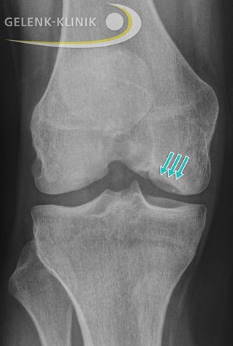

Die Röntgenaufnahme des Knies zeigt den Knochendefekt nach Ablösung des Dissekats. © Gelenk-Klinik

Das betroffene Kniegelenk wird in 2 Ebenen geröntgt. Dabei werden eine a.-p. Aufnahme (anterior-posterior, d. h. der Strahlengang verläuft von von vorne nach hinten durch das Kniegelenk) und eine seitliche Aufnahme des Kniegelenks angefertigt. Das Röntgen sollte unter Belastung des Gelenkes erfolgen, das heißt der Patient steht bei den Aufnahmen. Erst bei fortgeschrittenem Knochensterben (Nekrose) wird Osteochondrosis dissecans im Röntgenbild sichtbar. Dennoch ist eine indirekte Beurteilung des Knorpels im Kniegelenk möglich. Ist der sichtbare Gelenkspalt im Kniegelenk bei der Aufnahme im Stehen eingeengt, deutet dies indirekt auf eine abnehmende Festigkeit und Menge des vorhanden Knorpels hin. Die Röntgenaufnahmen können auch eine bestehende Achsfehlstellungen der Beine darstellen.